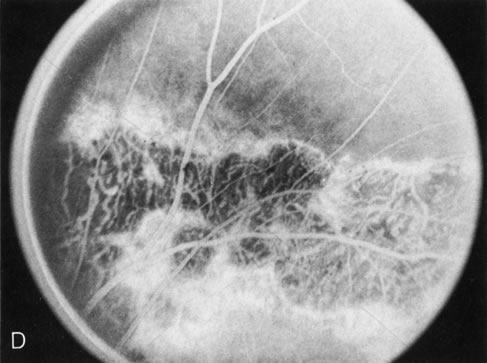

In retinitis pigmentosa (RP), the pigment abnormalities of atrophy, migration, and clumping are made apparent by transmitted hyperfluorescence and blocked hypofluorescence (Fig. 1A). Patients who have very minimal pigmentary alterations (pauci pigmentary RP) or no pigment abnormalities (RP sine pigmento) may show the abnormalities on fluorescien angiography (FA). It is uncommon to see choriocapillaris atrophy except in the late stages. This finding corresponds to the histopathology, which shows that the earliest abnormalities are in the photoreceptors and that the choroid is normal.1

Fig. 1. Retinitis pigmentosa. A. A typical area of bone spicule pigmentation. B. Diffuse dye leakage is apparent throughout the posterior pole. C. The early angiogram shows dilated and irregular retinal radial peripapillary capillaries and perifoveal retinal capillaries. D. Leakage from these vessels are evident in the late angiogram.

Dye leakage in RP may occur from the retinal vessels or at the level of the retinal pigment epithelium (Fig. 1B).2–4 The leakage may be seen in the macula and posterior pole, along the vascular arcades in the distribution of the radial peripapillary capillaries, and in the periphery (where an exudative vasculopathy resembling Coats' disease is suggested).

Of more clinical importance is the role of FA in the diagnosis and treatment of cystoid macular edema (CME) (Fig. 1C and D). Stereoscopic FA indicates that the leakage, which may be diffuse or have the typical petaloid stellate appearance of CME, can come from the perifoveal retinal capillaries, from the choroid through the RPE, or from a combination of both sources.4 With the recent suggestion that CME in RP may be successfully treated with acetazolamide,5, 6 FA is thus important to document the diagnosis of CME, establish the origin(s) of leakage, and follow patients during and after therapy.